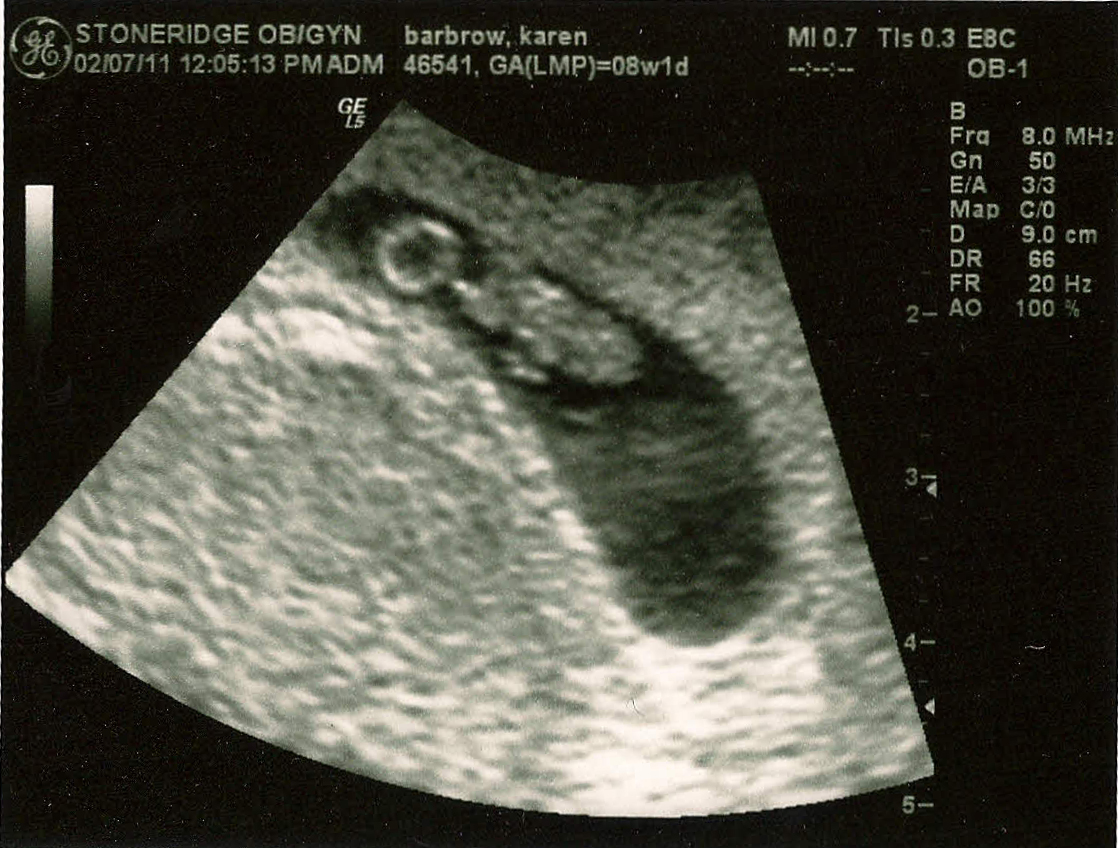

Jeremy and I are happy to announce that we're expecting our second child. Baby #2 is due September 22. The above ultrasound picture is from our 8-week appointment, where everything checked out just fine.